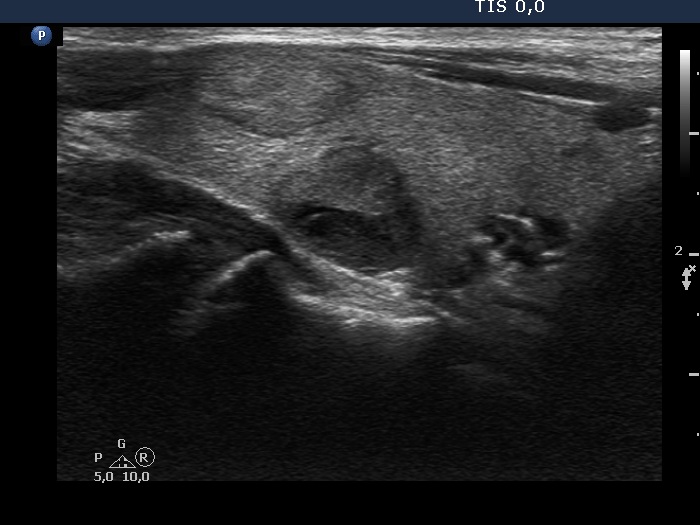

The echogenicity of the nodule - case 2120 (ultrasonographic picture 5)

Right lobe, longitudinal scan

Right lobe, another longitudinal view. The mass in the dorsal part is composed of multiple lesions.